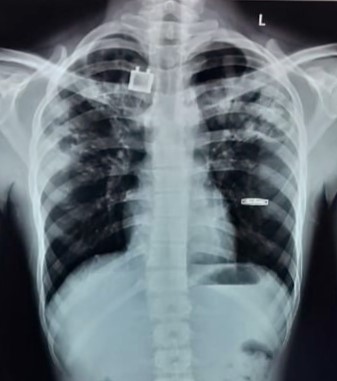

| 107 | IGGMC, Nagpur, Nagpur | P2 | 29-4365 | Vivek Indurkar | Consent taken on Paper | 36 Yrs. |

Provisional Diag : PTB Reactivation

Final Diag : Post TB With Reactivation |

TB Case (Confirmed) | Right lung fibro-bronchial and Fibro-calcific changes, fibro-cavitary changes In Right, Infiltration In Left Upper zone | Abnormality visible on x-ray |